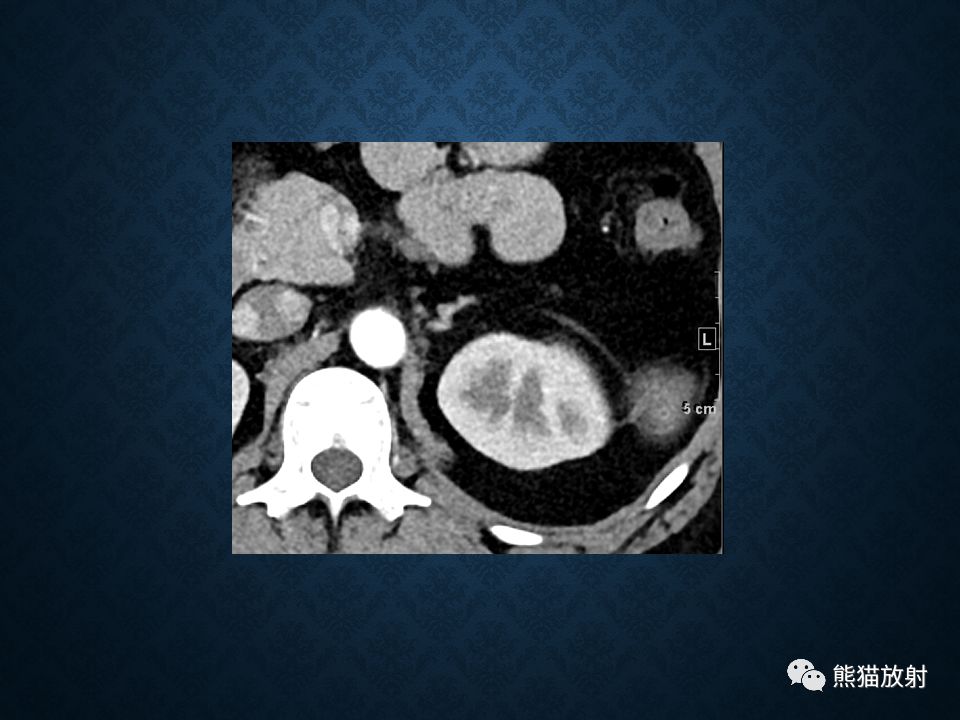

肾上腺常见肿瘤影像诊断

>腺瘤:临床表现决定于肿瘤的发生年龄,与 Cushing腺瘤表现相同,但无对侧萎缩改变

>皮质癌:约占30%

>先天性肾上腺增生:双侧肾上腺腺体显著弥漫性增大,程度常明显超过 Cushing综合征的皮质增生